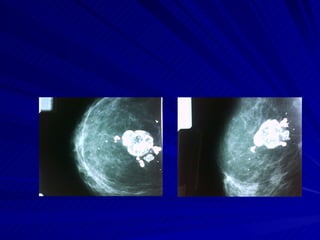

Calcificaciones mamarias Microcalcificaciones <2mm. Las importantes son <0,5mm. Distribución: son dispersas o  agrupadas >4x cm.(sospechosas) Formas: redondas, amorfas, heterogéneas, lineales irregulares o moldeadas. Redondas: probable benignas Microquísticas -benignas.  Macrocalcificaciones. >2mm. Vasculares. Lineales quísticas. Citoesteatonecrosis. Quiste oleoso. Pop-corn. Distróficas. Dérmicas. Ductales secretorias. Son benignas

Formas de microcalcificaciones Tipo 1:leche cálcica.” Tea cups”. 100% benignas. Tipo2:redondas. Generalmente benignas- Tipo3:polvorientas. Difíciles de evaluar.  Requieren biopsia. Tipo4:irregulares.  Son como granos de sal, siempre biopsia. Tipo5:moldeadas.  Siempre requieren biopsia

Microcalcificaciones sospechosas: Básicamente, cuando existen > de4 microcalcificaciones por cm2.

Calcificaciones mamarias Microcalcificaciones<2mm. Las importantes son <0,5mm. Distribución: son dispersas o agrupadas >4x cm.(sospechosas) Formas: redondas, amorfas, heterogéneas, lineales irregulares o moldeadas. Redondas: probable benignas Microquísticas -benignas. Macrocalcificaciones. >2mm. Vasculares. Lineales quísticas. Citoesteatonecrosis. Quiste oleoso. Pop-corn. Distróficas. Dérmicas. Ductales secretorias. Son benignas

Formas de microcalcificacionesTipo 1:leche cálcica.” Tea cups”. 100% benignas. Tipo2:redondas. Generalmente benignas- Tipo3:polvorientas. Difíciles de evaluar. Requieren biopsia. Tipo4:irregulares. Son como granos de sal, siempre biopsia. Tipo5:moldeadas. Siempre requieren biopsia

Microcalcificaciones sospechosas: Básicamente,cuando existen > de4 microcalcificaciones por cm2.